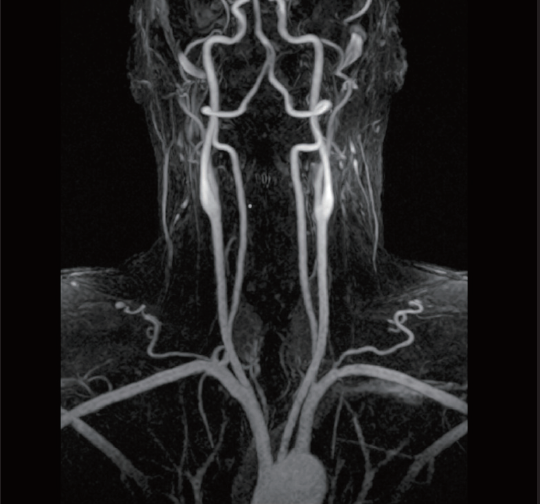

FLUTE eliminates the need for a timing injection. Users monitor the artery of interest for bolus arrival using real-time fluoro scanning mode, switching instantly to the 3D diagnostic scan upon arrival.

TRAQ depicts blood flow dynamics for simplified bolus MRA acquisition. Multiple 3D acquisitions are collected to visualize the entire blood flow cycle, thereby alleviating the need for precise timing of the contrast bolus.

VR is a reconstruction method that can be created on the console. It can determine blood flow movement stereoscopically to support diagnosis of regions with complex vascular structures such as the head.